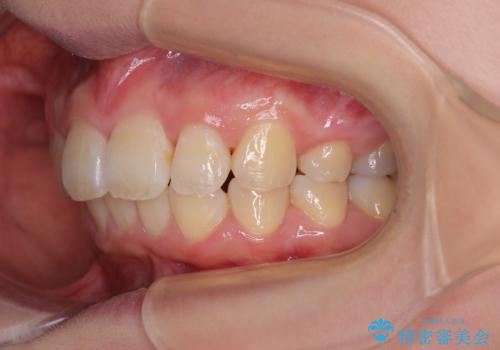

予想通りに治療は困難を極め、その上途中来院されない時期があったため、非常に長期間に及びましたが、周囲の方々が驚愕するほど口元の印象を改善することができました。